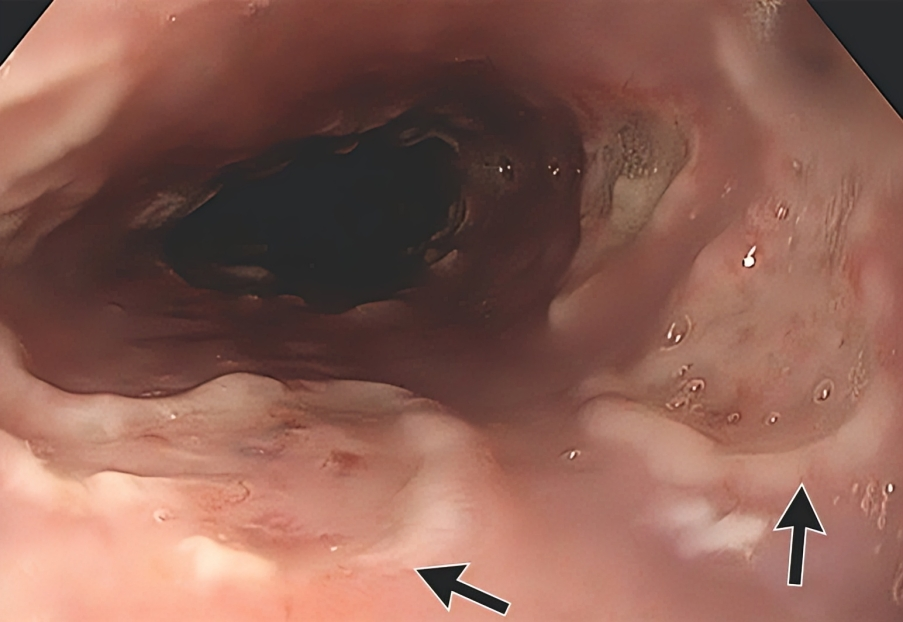

”56, female, presents with difficulty swallowing 140 days after allogeneic transplant for AML

GI scopes her, sees.

Path sees.

What’s going on?

Management?”